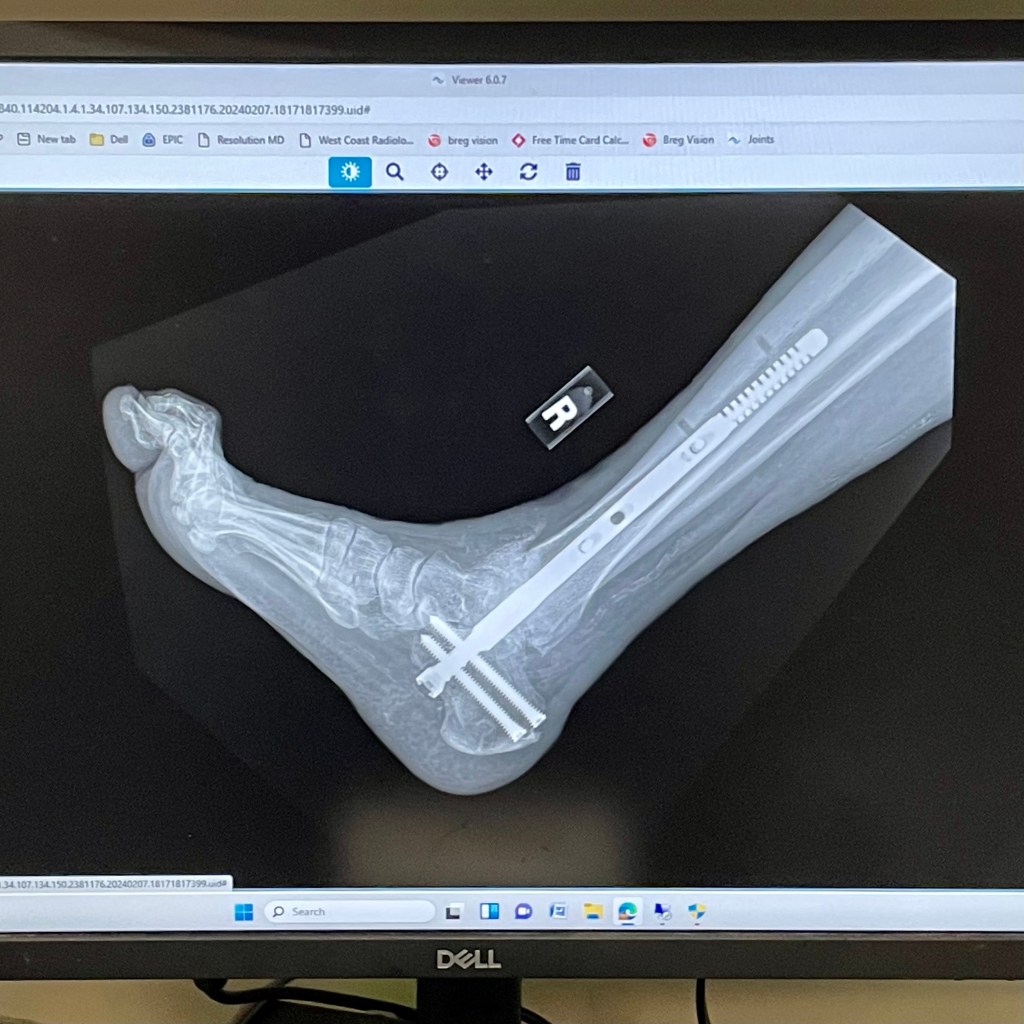

Ankle Update 20240207

I had my second follow-up appointment with the orthopedic surgeon today. After sawing off the cast, the surgeon said it look good healing-wise, and sent me off to get some x-rays.

I think they took four x-rays and it confirmed that my ankle is healing well. The surgeon even told me that I may switch to a walking boot during the next visit. I am not setting any expectations.

I got a nice new blue cast this time. The surgeon even got some alcohol pads and wiped down my lower right leg. It has been in a splint and cast forever so the skin was dry and probably stinky.